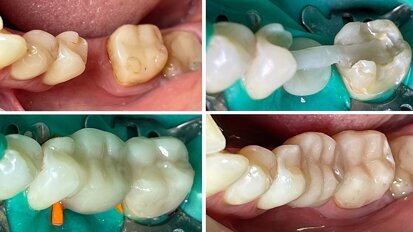

Restauración clase II con composite termoviscoso

Este artículo del Dr. Yassine Harichane, experto en odontología estética, destaca la forma de trabajar con composites termoviscosos en una situación ...